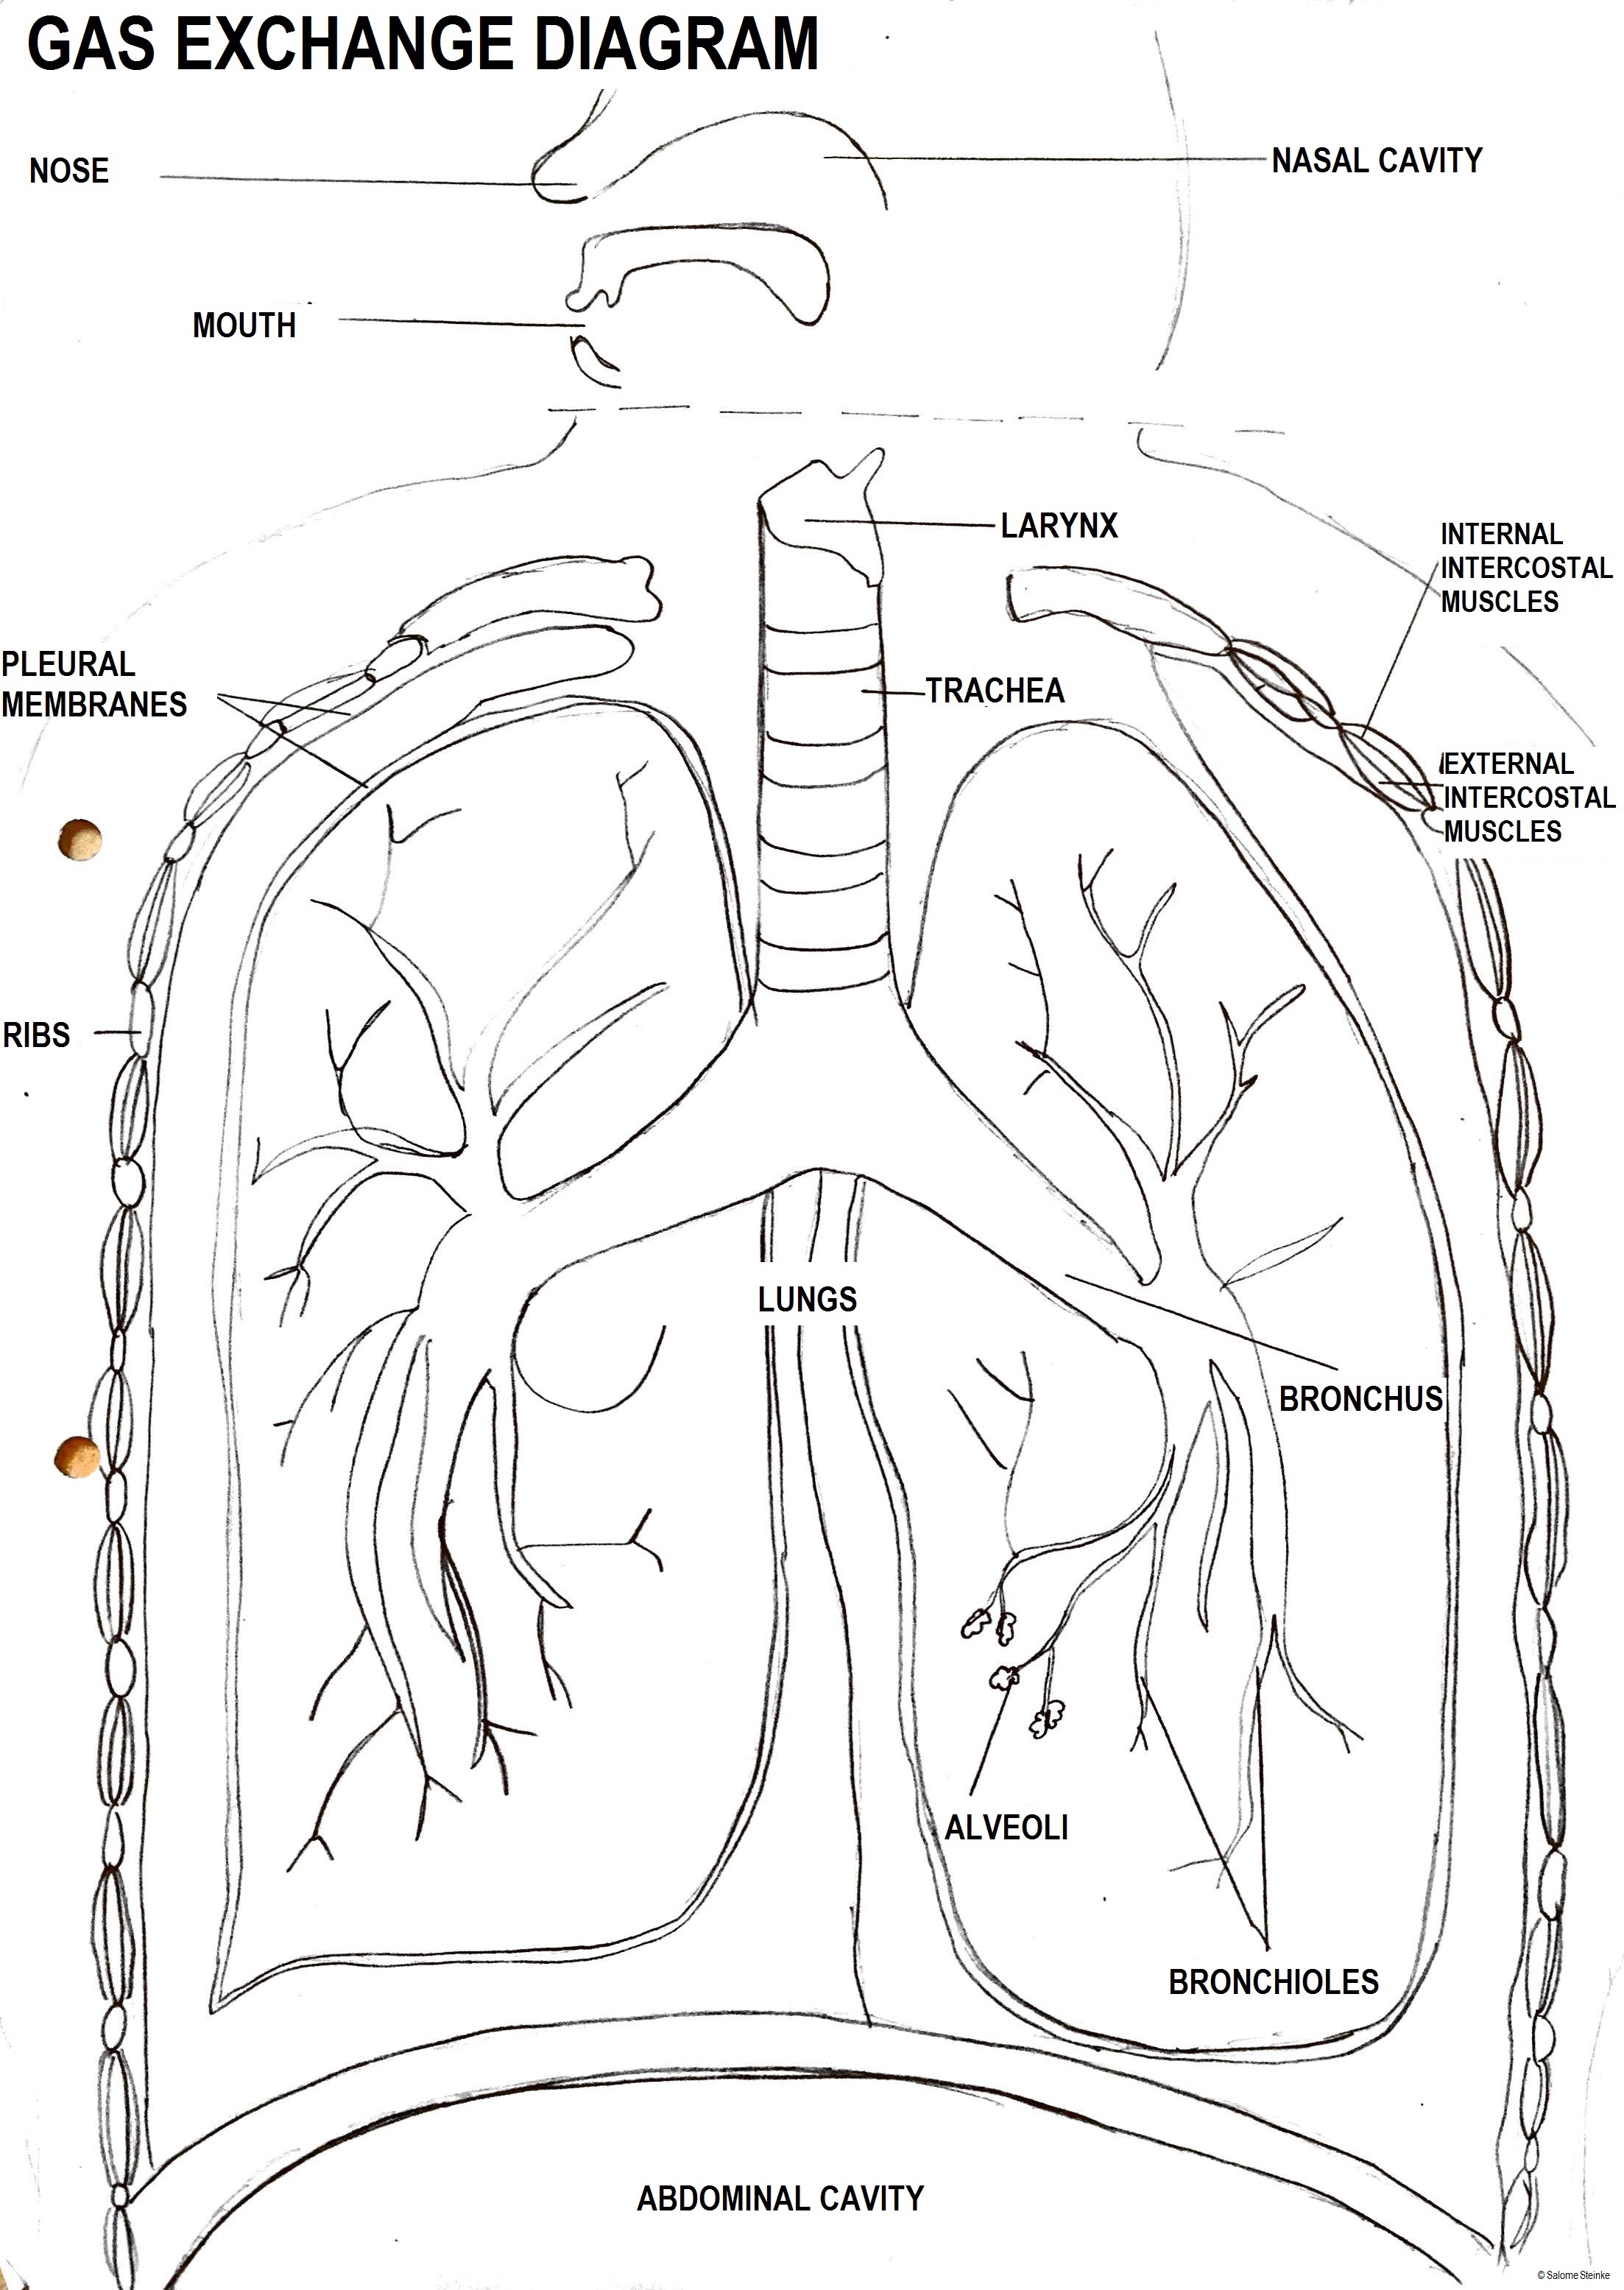

- Draw a diagram to show the structure of an alveolus and an adjacent capillary. Alveoli consist of two types of pneumocytes;

- Type I are extremely thin and are adapted to carry out gas exchange.

- Type II secrete a solution containing surfactant that creates a moist surface inside the alveoli. This reduces surface tension and prevents the sides of the alveolus sticking to each other.

- The trachea and bronchi carry air to the alveoli in bronchioles in the lungs.

- Muscle contractions cause the pressure changes inside the thorax that force air in and out of the lungs to ventilate them.

- External and internal intercostal muscles, and diaphragm and abdominal muscles are antagonistic muscles, required for inspiration and expiration because muscles only work by contracting.